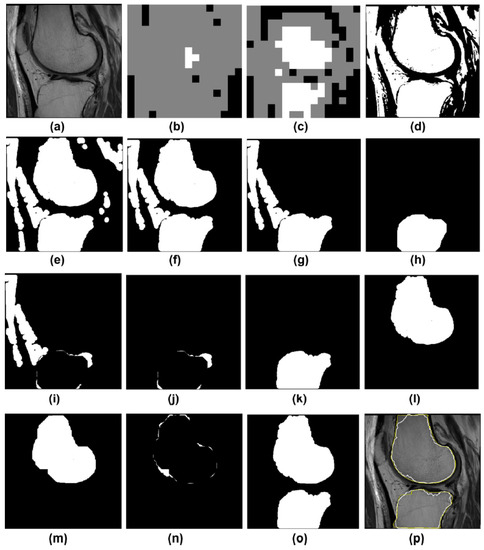

Figure 4.

An example illustrates both ROI detection failures/recoveries and leak detection and correction. (a) An MRI image; (b) the ROI block is detected with only the femur bone detected, not the tibia; (c) after lowering the ROI detection threshold, both bones are detected; (d) mask for the GC output; (e) after morphological processes; (f) the resulting two potential skeletons, with a leak seen in the tibia bone; (g) the tibia bone has a leak that connects fat and other tissues to the tibia; (h) initial step in detecting a leak is to use a morphological opening; (i) residual content resulting from subtracting (h) from (g). (j) Following an examination of the remains in (i), the leak detection method identifies a leak and decides that only the pixels in the leak are affected; (j) are relevant to the tibia (k) after adding the appropriate pixels in (j) to (h), resulting in a leak-free tibia (i), the femoral mask (l) and (m). After applying the morphological aperture to check for leakage (n) the remaining pixels after subtracting (m) from (i). On this basis, it is concluded that there is no leak, and the pixels are reinserted (o). (o) femur and tibia masks as a result (p) GC segmentation in white and manual segmentation in yellow determined with DICE = 0.95 and 0.96 resolution for femur and tibia bones, respectively [45].